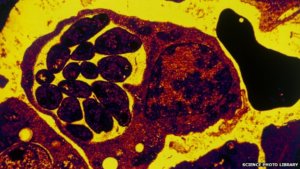

Malaria

Scientists all over the world are searching desperately for a malaria vaccine. In 2013 up to 2.7 billion dollars were given to research projects worldwide. But as long as the vaccine is not found, the World Health Organization (WHO) recommends artemisinin-combination therapies (ACT) as the only reliable means to treat malaria patients.

In Asia, the pathogen has already developed resistance to drugs based on artemisinin. Should this happen in sub-Saharan Africa, where about ninety percent of all cases of malaria occur, it would be a kind of 'meltdown' for the healthcare systems of the countries concerned.